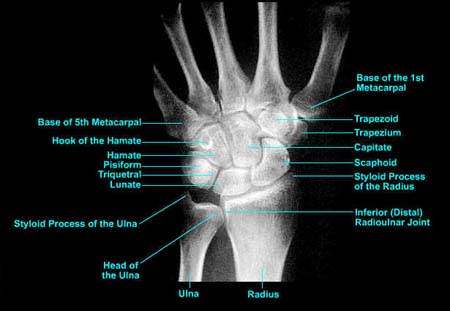

Wrist PA image